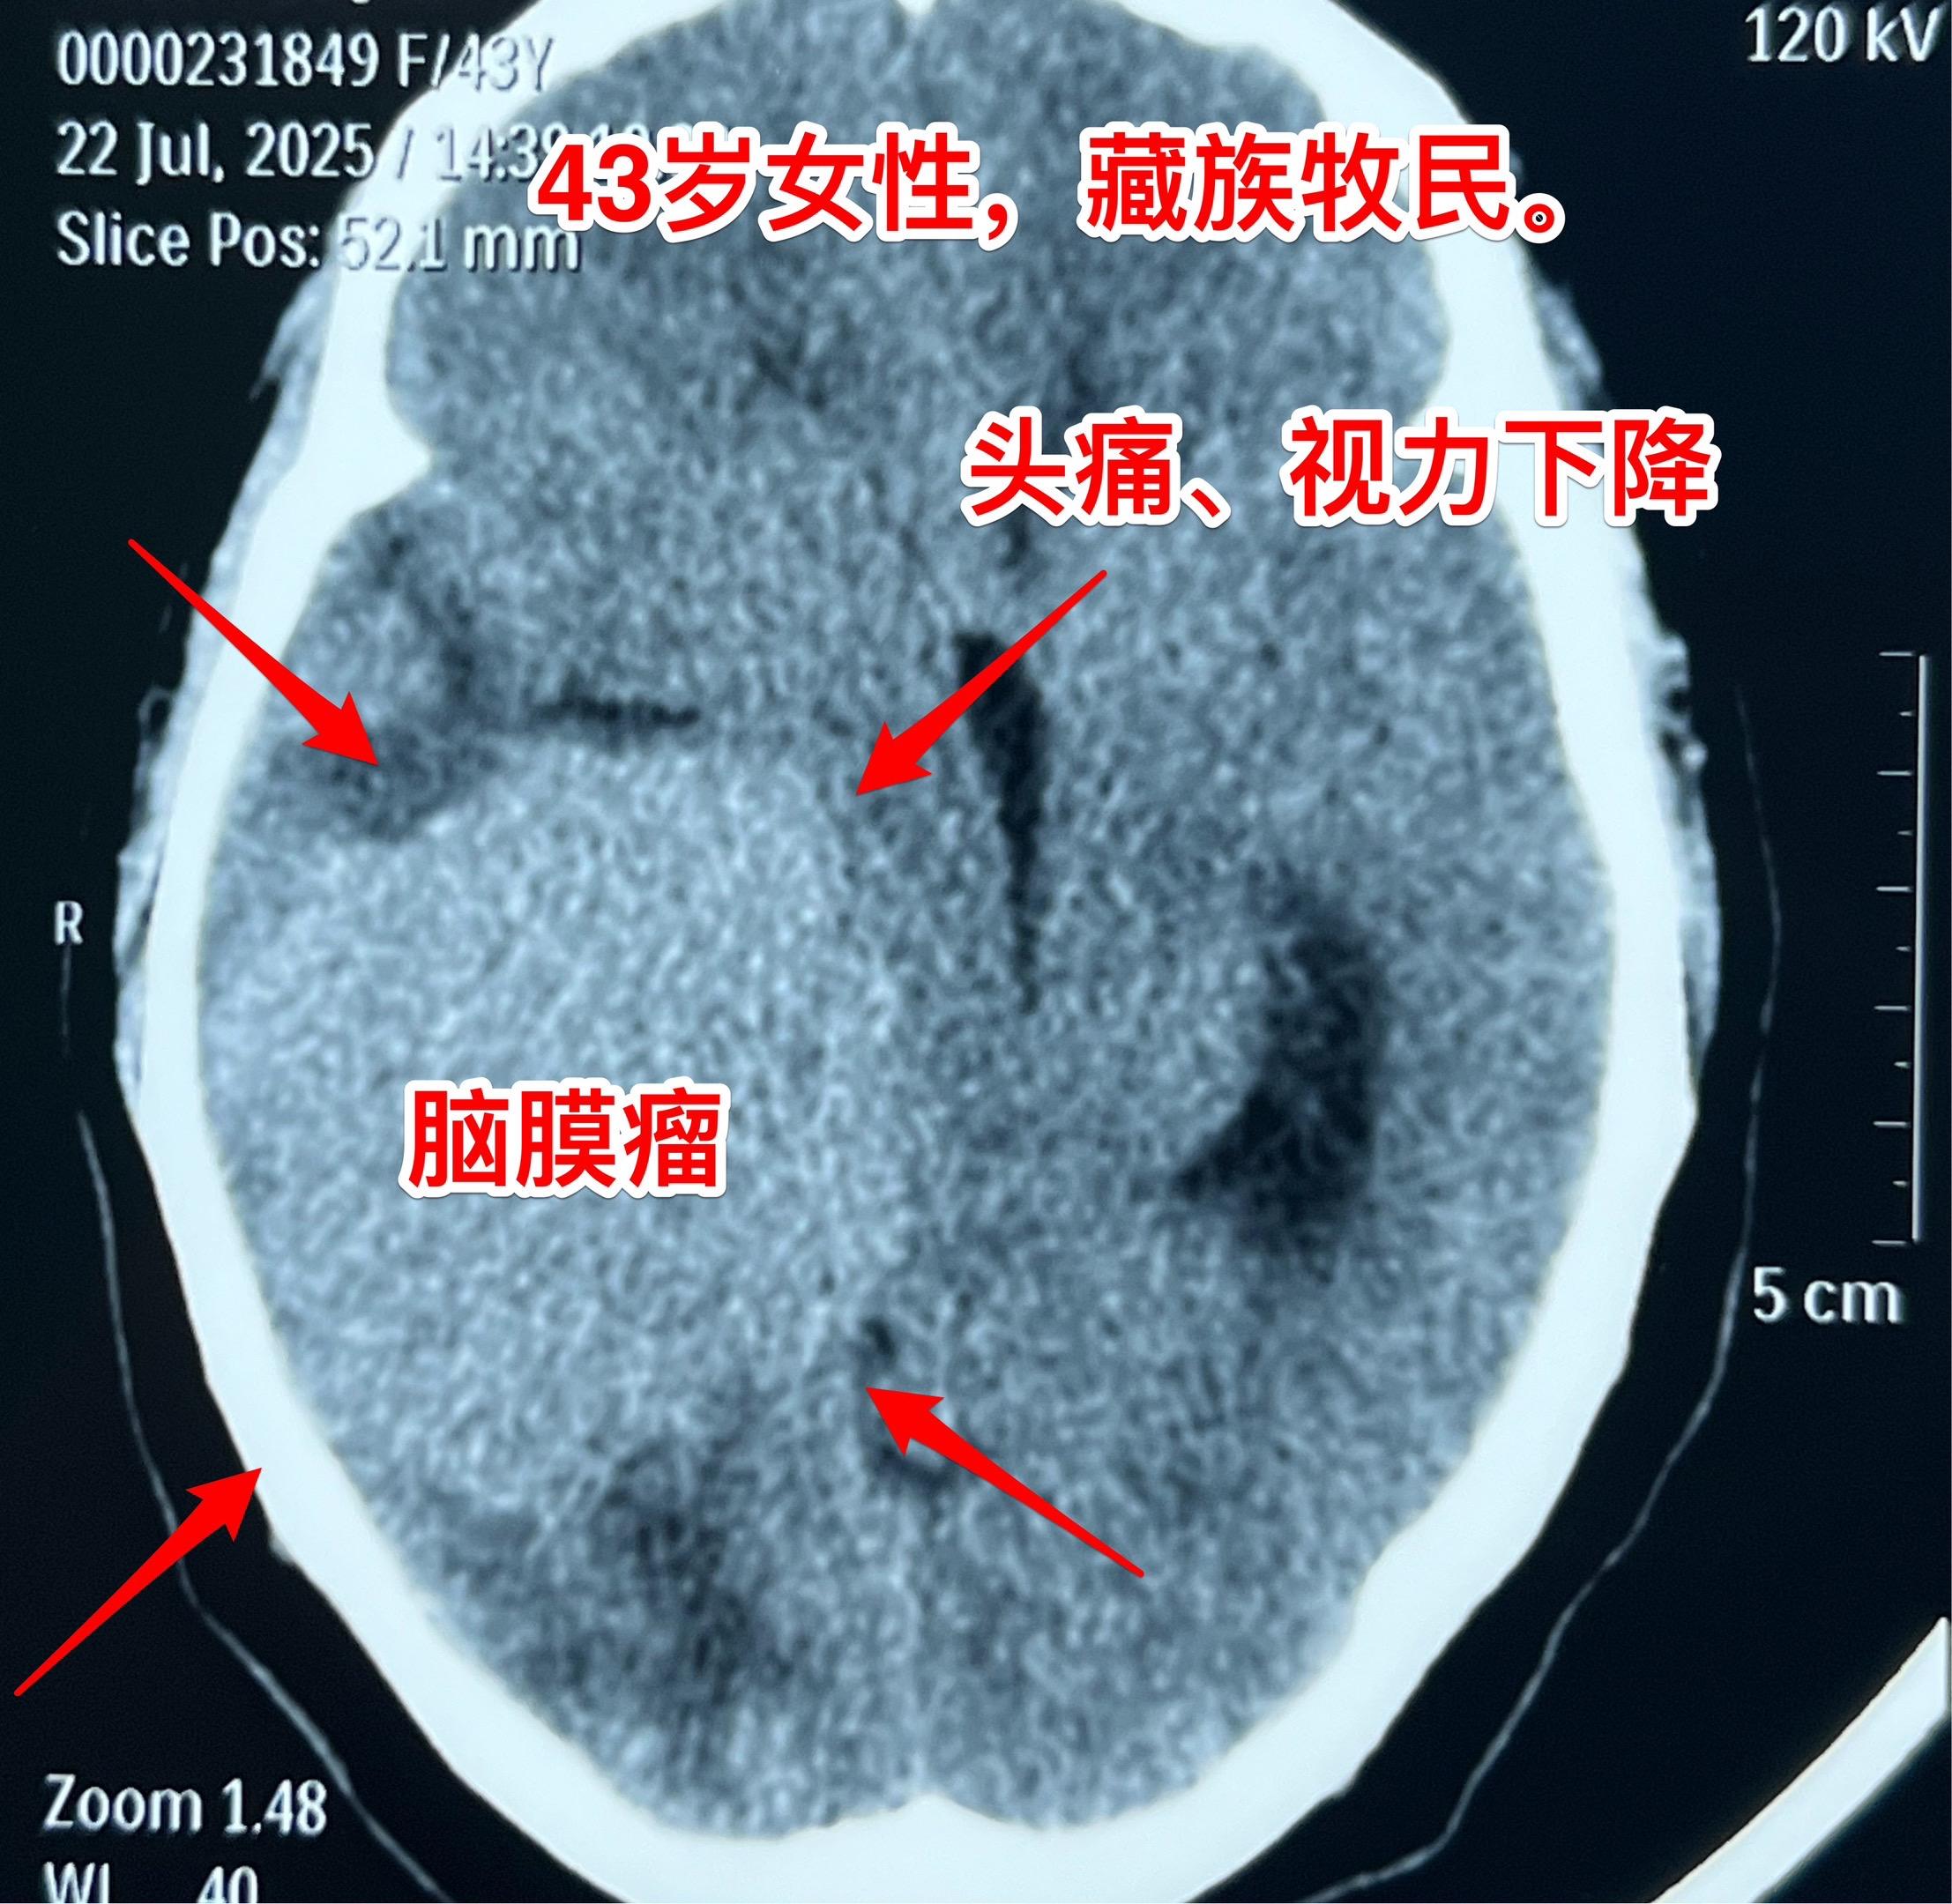

藏族牧民脑肿瘤被发现时像鸡蛋一样大。青海省黄南州藏族牧民,43岁,女性...